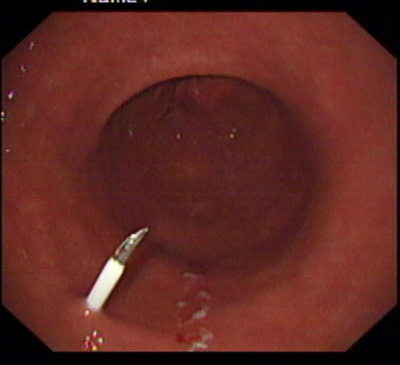

在消化科董蕾主任关心和指导下,消化科王进海教授,张利医师成功地给一位脑出血后吞咽困难的患者实施了经皮内镜下胃造瘘术。

该患者系男性,76岁,脑出血后留有吞咽困难后遗症,不能自主进食,需长期留置胃管供给营养,严重的影响了病人的生活质量和原发病的恢复。经皮内镜下胃造瘘术(Percutaneous endoscpic gastrostomy,PEG)是一种无需常规外科手术和全身麻醉的造瘘技术,可以在胃镜室或病房局麻下进行,因此是一种操作简便、创伤小、安全可靠的方法。该例患者在胃镜室局麻下进行手术,手术过程约10分钟,术后病人无明显不适,3天后即可从造瘘管给食物并出院。

该手术的成功填补了院内空白,丰富了内镜下治疗的内容。对于各种原因造成的长期或较长期不能(一月以上)经口进食者,可通过造瘘管供给病人足够的营养物质,效果优于传统的鼻胃管饲营养,费用又明显低于静脉内营养,是一项值得推广的内镜下较为安全的治疗技术。经皮内镜下胃造瘘术适应证包括:①中枢神经系统或全身性疾病导致的吞咽困难或不能吞咽。如:脑干炎症、变性,脑血管意外,脑肿瘤, 脑外伤;急性呼吸衰竭;系统性硬化症、重症肌无力;完全不能进食的神经性厌食或神经性呕吐导致严重的营养不良,而不能耐受手术造瘘者;②口、咽、喉手术前后及头颈部肿瘤放疗期间,需较长时间营养支持者。③食管广泛瘢痕者;④严重的胆外瘘需将胆汁引回胃肠道者;⑤各种原因所致呼吸功能障碍须气管切开,同时需PEG者;⑥胃肠减压(一月以上的鼻胃管留置者)的目的。